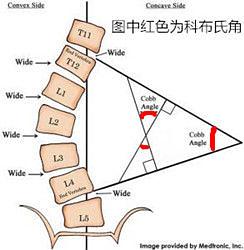

科布氏角是用來定義脊柱側彎在冠狀面上的角度,從而說明脊柱側彎的嚴重程度。下圖就是對脊柱側彎患者全脊柱X光的一個Cobb’s角度測量!誤給別人扣上了脊柱側彎的帽子!!!!!